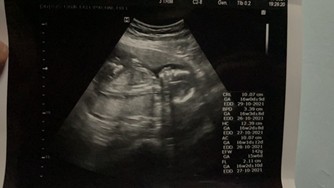

ตอนนี้จะเข้า 12. สัปดาห์แล้ว คุณแม่ท่านไหน คลอด เดือนพฤศจิกายน เหมือนกันบ้างมั้ยคะ ❤️😚🤰🏻👶🏻